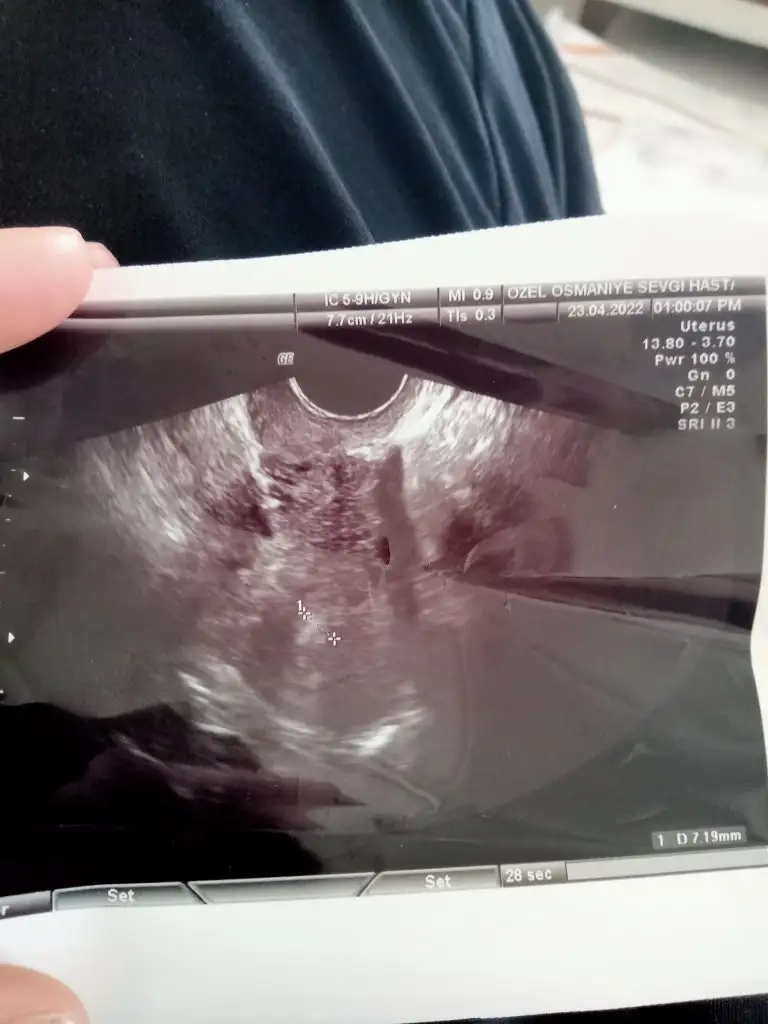

Canımlar bende şimdi çıktım Malesef çok iyi haberlerim yok. solda 13 mm yumurtam var şimdilik yeterli büyüklükte değil e2 verdim sonuç 2 saate çıkar gonalf 100 vurucam pazartesiye kadar. Pko var çok yumurta oluşur diye korkuyordu doktor nerdeyse hiç büyümemiş az biraz bozuldum